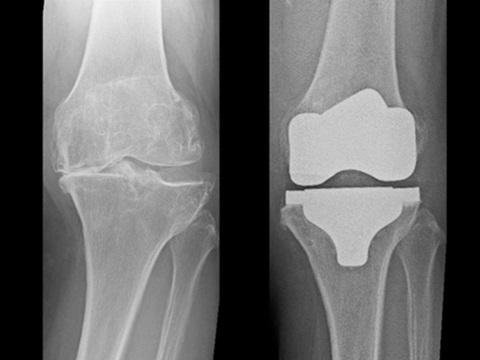

変形性膝関節症に対する手術

膝の痛みの原因の一つに膝関節の変形(変形性膝関節症)があります。多くは長年膝を使ってきた事によりますが、事故や怪我などによる膝関節のクッションの役割をする半月板や軟骨、膝の靭帯の損傷が引き金となる場合もあります。基本的にはヒアルロン酸注射やリハビリテーションを用いた保存治療を行います。しかし、痛みが続く場合には、変形の程度や患者さんの生活状況などによって、当院では下記のような手術を行っています。

「人工膝関節置換術(TKA:Total Knee Arthroplasty)」

TKAは、膝関節全体を人工関節で置き換える手術方法であり、膝関節の変形が進行している場合に適しています。痛みや歩行能力が改善するだけでなく、見た目の変形も改善するため、「足がまっすぐになった」と喜ばれる患者さんも多いです。

UKAに比べると侵襲が大きいため、入院期間は1~2ヶ月程となります。手術後の痛みや不安定感の改善が期待できる一方、手術には大きな切開が必要であり、UKAに比べるとややリハビリ期間が長く、手術後のリスクもUKAよりも高めとされています。

HTOやUKAよりも変形が強い方が対象です。